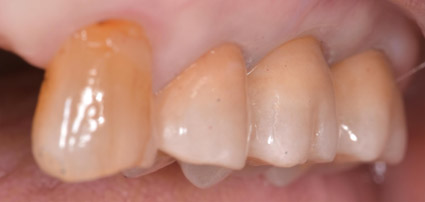

ファイナル

リハビリ期間を経て最終的な補綴物を製作します。審美的、機能的な要件を満たすべく技工士とコミュニケーションをとります。